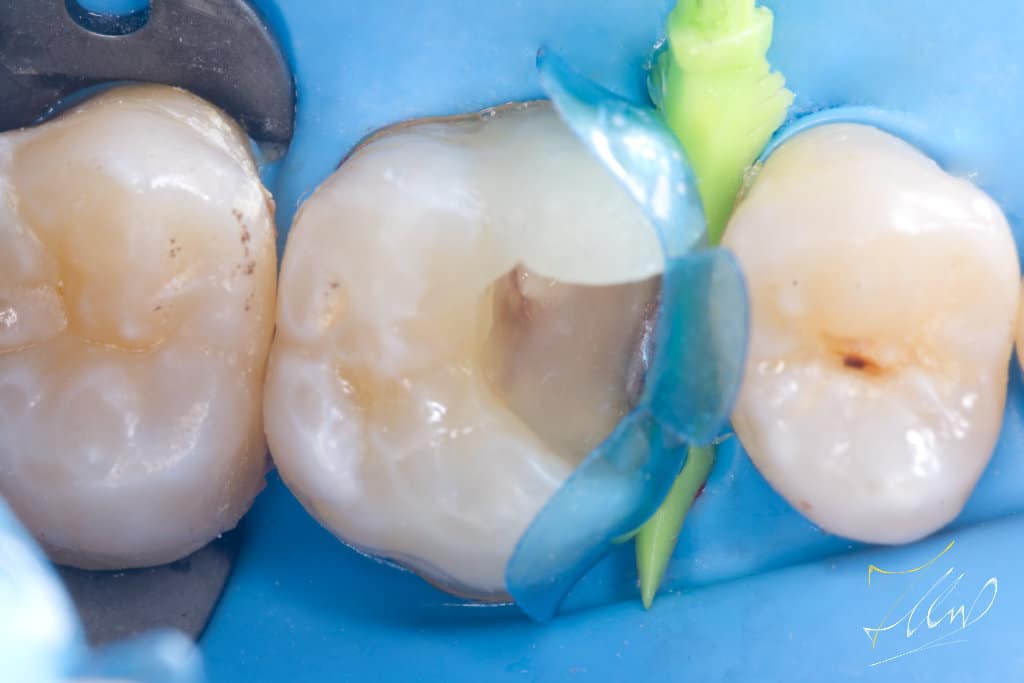

To facilitate matrix placement and achieve optimal contact and contour, it is essential to restore the buccal wall to its original shape.By marking the lost structure and build the buccal cusp to enhance the structure, consider reinforcing the buccal cusp with composite material and then inserting FRC (ever x) to effectively manage the separation force of the ring without compromising the integrity of the composite.

The blue bio fit matrix was chosen .Together with anatomical deep caries wedge to get the optimal fit.

Restoring the proximal margin.